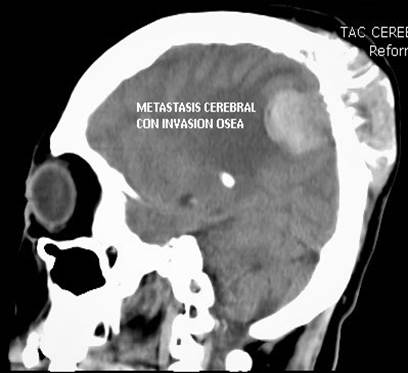

Ilustración 8 Ca de tiroides y metástasis cerebral.

Fuente: Hospital de Especialidades Guayaquil “Doctor Abel Gilbert Pontón”.

Autor: Dr. Fernando Moncayo A.

Paciente de 68 años de edad, que ingresa referida de otra institución por presentar más tumoral en región occipital derecha de gran tamaño dura muy adherida, dolorosa con circulación colateral; paciente desorientada en tiempo y espacio, irritable y poco colaborativa, en algunas ocasiones ha presentado convulsiones tónico clónicas. Además, presenta masa cervical voluminosa, a nivel tiroidea, dura, adherida a estructura aéreas y vasculares.

Se toma biopsia con aguja gruesa de lesión tumoral cervical y tumoración occipital encontrando carcinoma papilar variante oncocitica.  Paciente fue tratada por el departamento de oncología clínica en forma paliativa y con Sorafenib por no haber mejoría con radio-yodo.